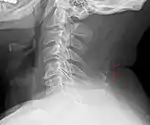

Other locations

Bone tissue in the nuchal ligament.

Neck